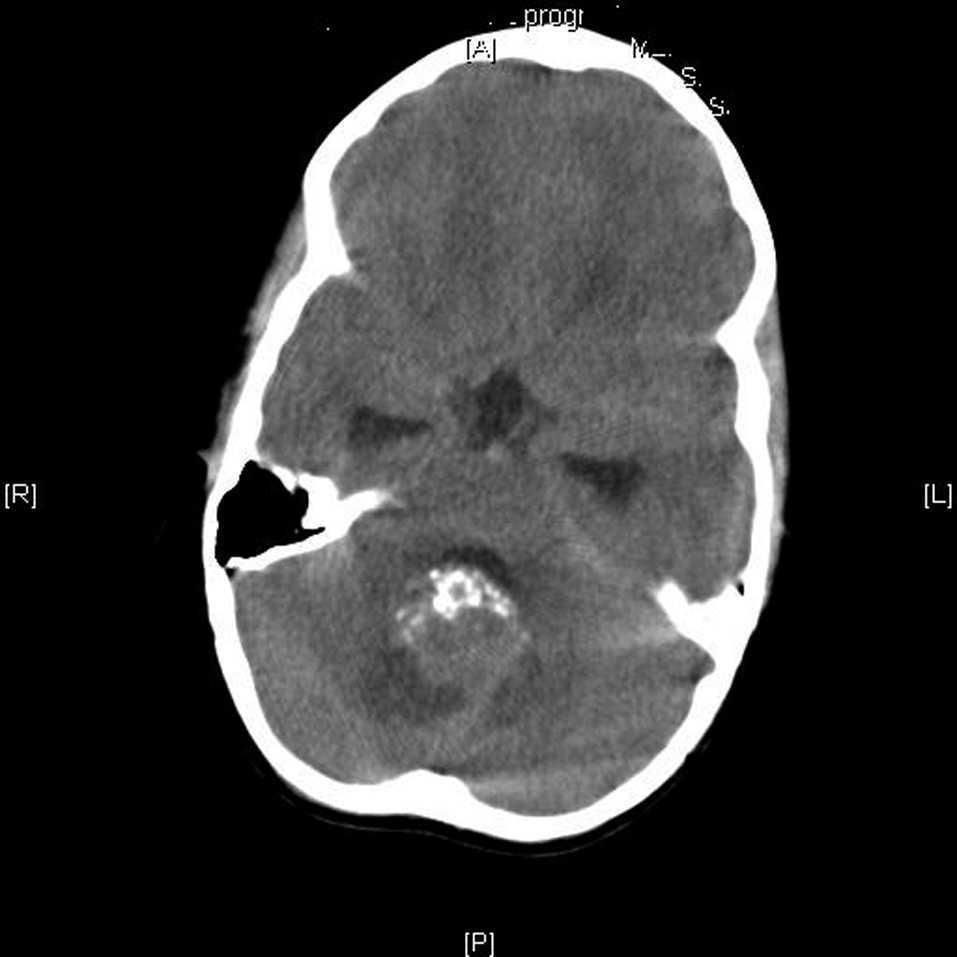

La tomografía computarizada (TC) cerebral con contraste mostraba una tumoración en el techo del cuarto ventrículo con calcificaciones, edema perilesional e hidrocefalia triventricular (fig. 1). Las resonancias magnéticas (RM) cerebral y de neuroeje con gadolinio confirma la presencia de la tumoración con una alta sospecha de ependimoma (fig. 2).

Figura 1.TC craneal con contraste al diagnóstico. Tumoración en el techo del cuarto ventrículo con calcificaciones, edema perilesional e hidrocefalia triventricular.